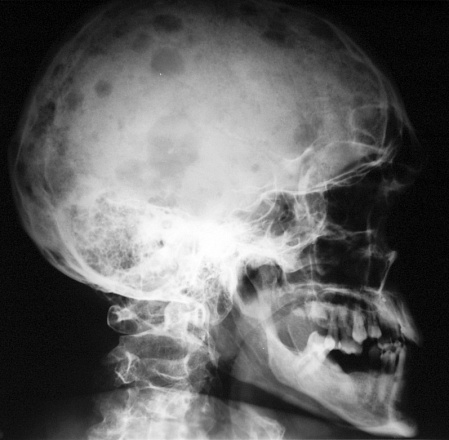

Миеломная болезнь: диагностика

При подозрении на миеломную болезнь специалисты нашей клиники назначают пациенту комплексную диагностику. В первую очередь проводится осмотр, во время которого врач пальпирует болезненные области. После этого требуется:

• рентгенография таза, черепа, грудной клетки;